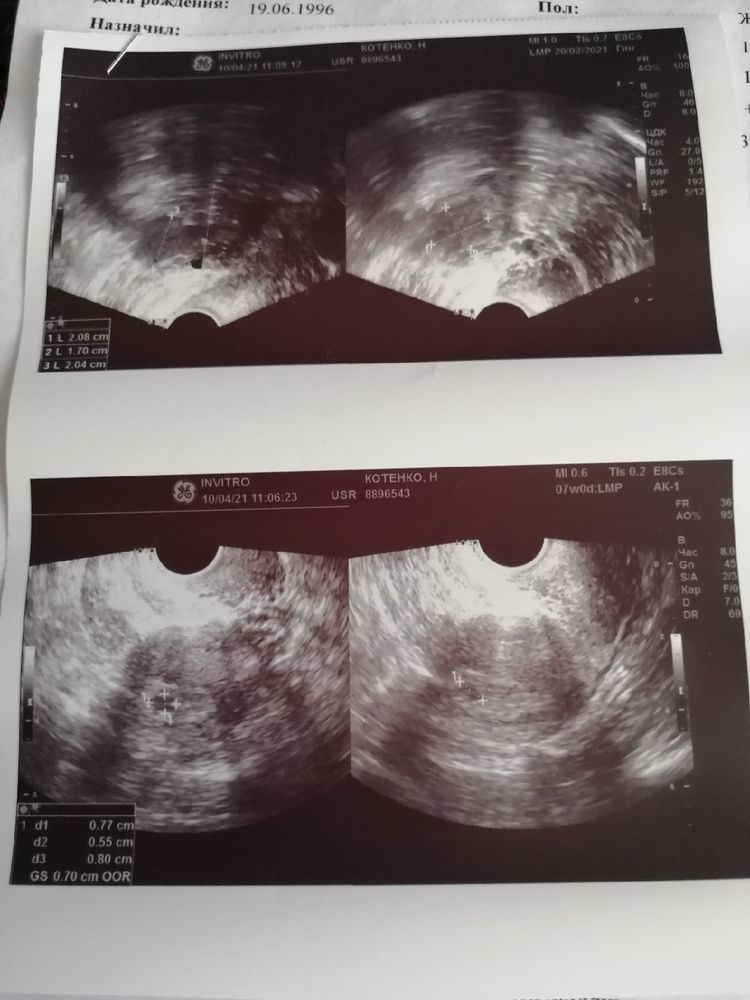

Наше первое УЗИ 💖

Не правильно я считала срок, сбил с толку мой длинный цикл. В общем то у меня 3-4 недели эмбриональные или 5 акушерских недель. Эмбриончика пока нет, поэтому еще через 2 недели на повторное)

Плодное яйцо в матке, все хорошо. Выделения хорошие, болей никаких нет.